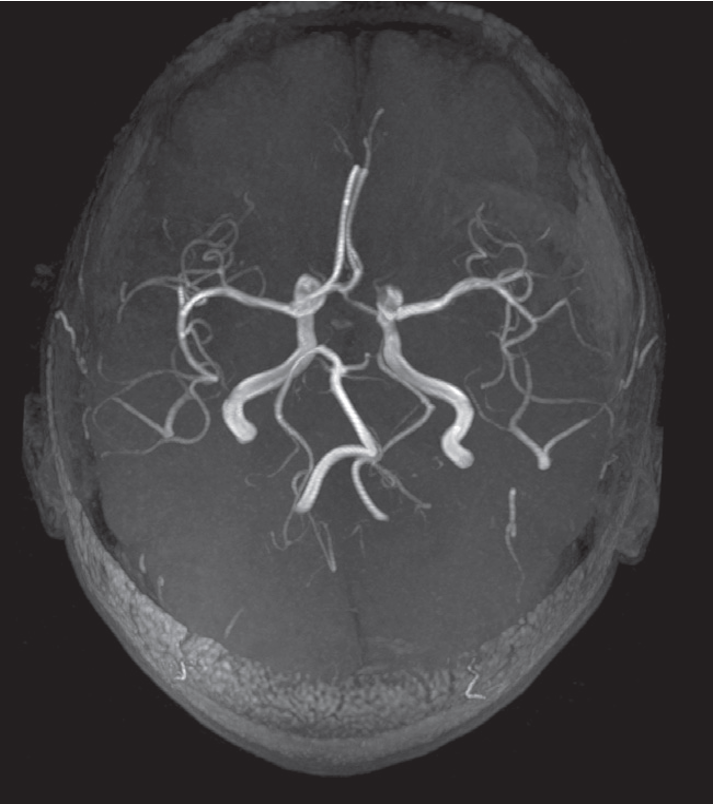

Magnetic resonance angiography (MRA)

The arteries at the base of the brain, the circle of Willis, are very well shown by MRA without the use of any contrast agent.